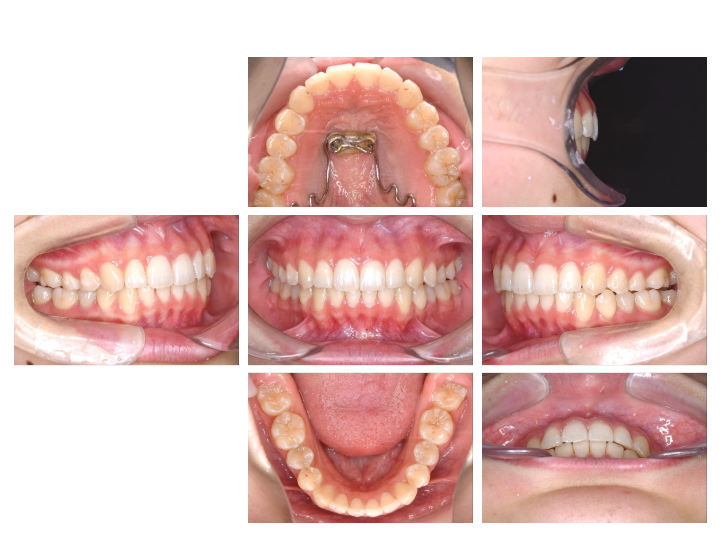

第2期治療

歯の1本1本に装置をつけ、歯の根までコントロールして最終的な咬み合わせを作ります。